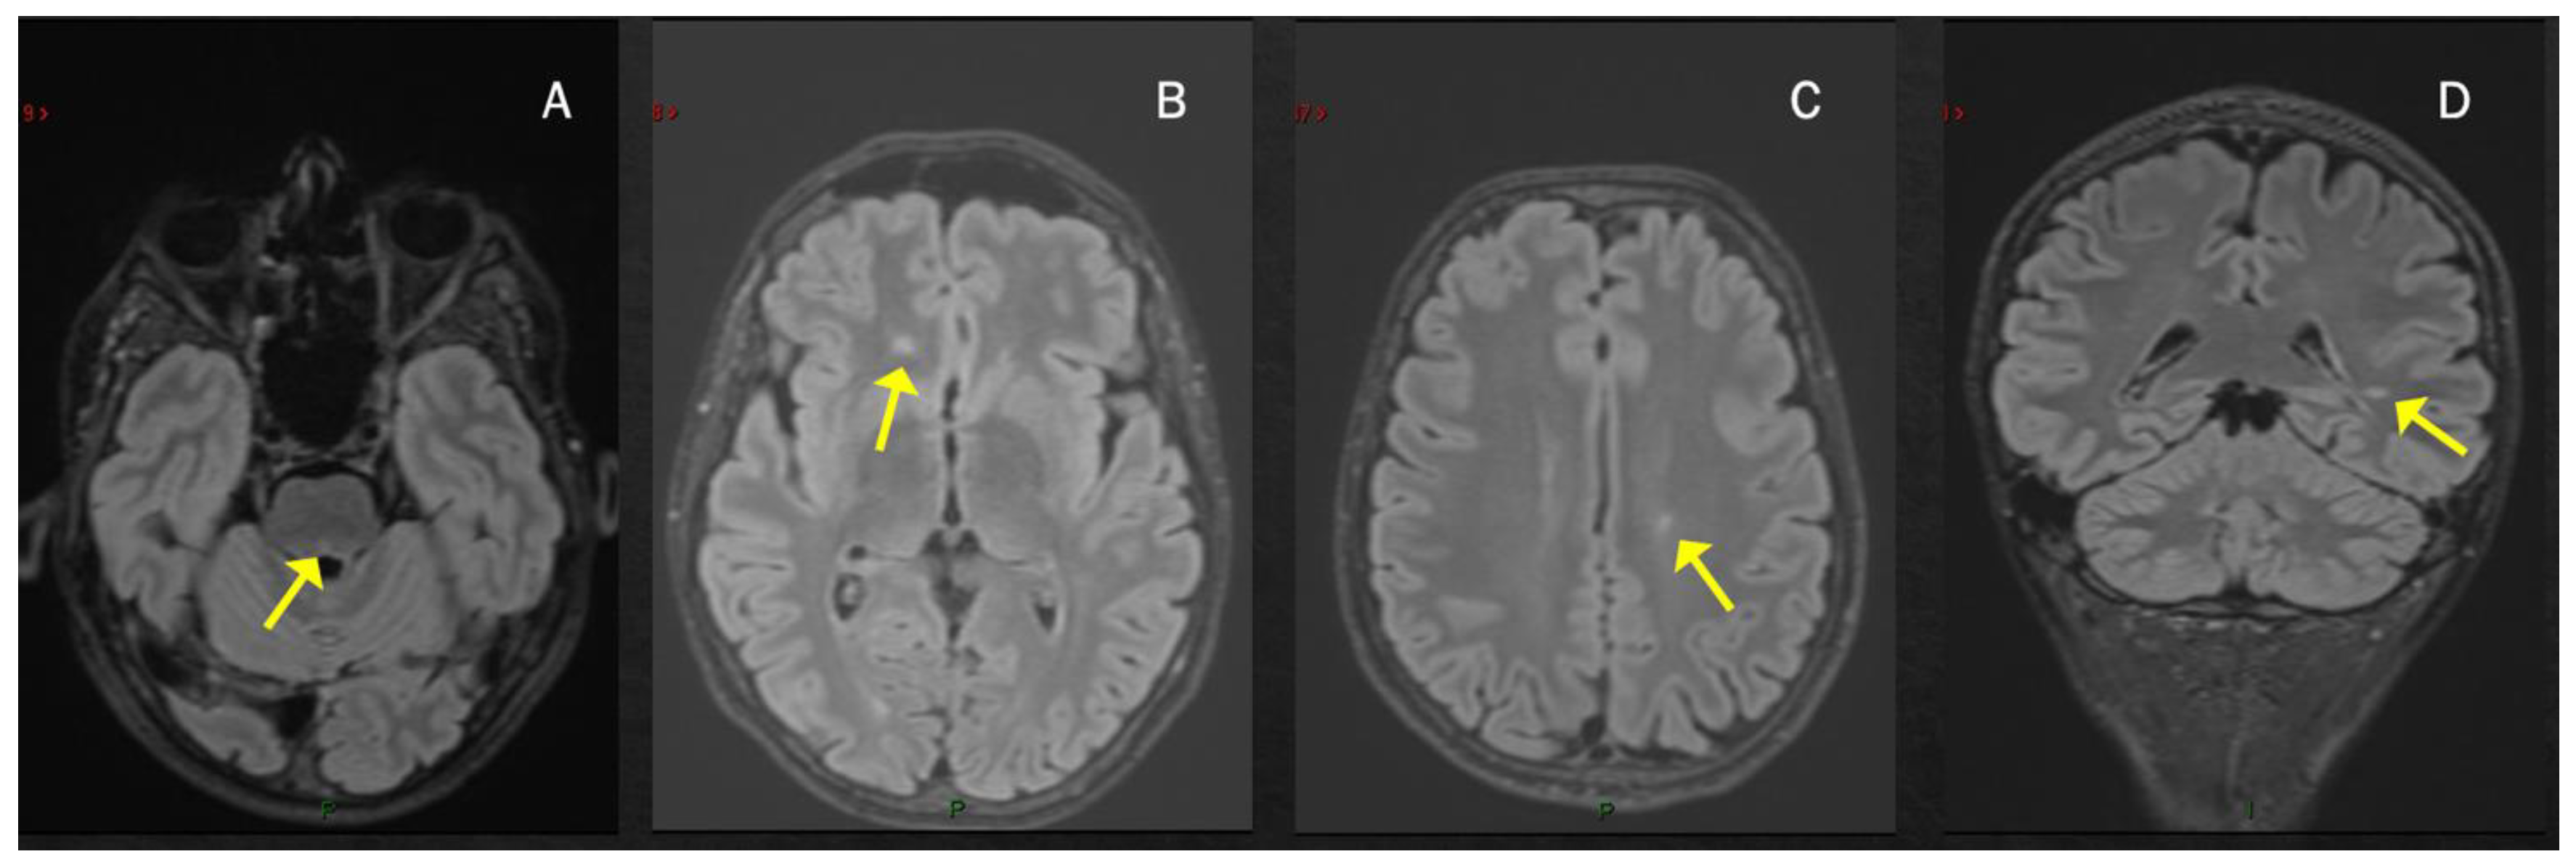

2. MS Onset after SARS-CoV-2 Exposure

| Case 1 | 2 weeks | BS (dyplopia) | - | + | + | - | +/+ |

| Moore et al. [52] | 2 weeks | BS (dyplopia) | BS, ST | + | + | NA | +/+ |

| Yavari et al. [53] | 3 weeks | BS (dyplopia) | ST | + | NA | NA | -/- |

| Carta et al. [54] | concomitant | BS (dyplopia) | ST ^ | + | NA | -/- | |

| Pignolo et al. [55] 1st case | 8 weeks | BS (facial palsy) | - | + | + | - | +/+ |

| Ismail et al. [76]. | 8 weeks | Cerebellum | - | + | + | - | -/- |